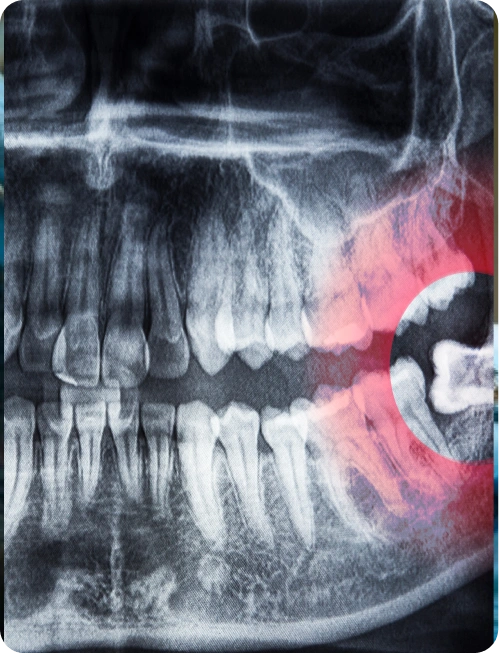

Der Zahnarzt bei nova-smile entscheidet, ob ein Weisheitszahn entfernt werden muss, basierend auf mehreren Faktoren. Dazu gehören die Position des Zahns, ob er vollständig durchgebrochen ist oder nicht, und ob er Beschwerden, Schmerzen oder Infektionen verursacht. Auch die Auswirkungen auf benachbarte Zähne und die allgemeine Mundgesundheit spielen eine Rolle. Röntgenaufnahmen helfen, die Lage und den Zustand der Weisheitszähne zu beurteilen. Wenn der Weisheitszahn das Risiko von Zahnverdrängungen, Karies oder Zahnfleischerkrankungen erhöht, wird eine Entfernung oft empfohlen, um zukünftige Komplikationen zu vermeiden.